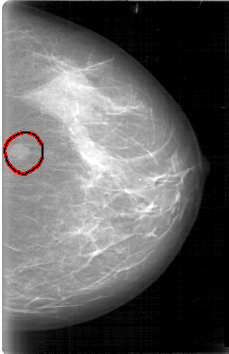

D_4006_1.LEFT_CC

LEFT_CC LINES 5296 PIXELS_PER_LINE 3421 BITS_PER_PIXEL 12 RESOLUTION 43.5 OVERLAY

FILE: D_4006_1.LEFT_CC.OVERLAY

TOTAL_ABNORMALITIES 1

ABNORMALITY 1

LESION_TYPE MASS SHAPE OVAL MARGINS OBSCURED

ASSESSMENT 0

SUBTLETY 5

PATHOLOGY BENIGN

TOTAL_OUTLINES 1

BOUNDARY